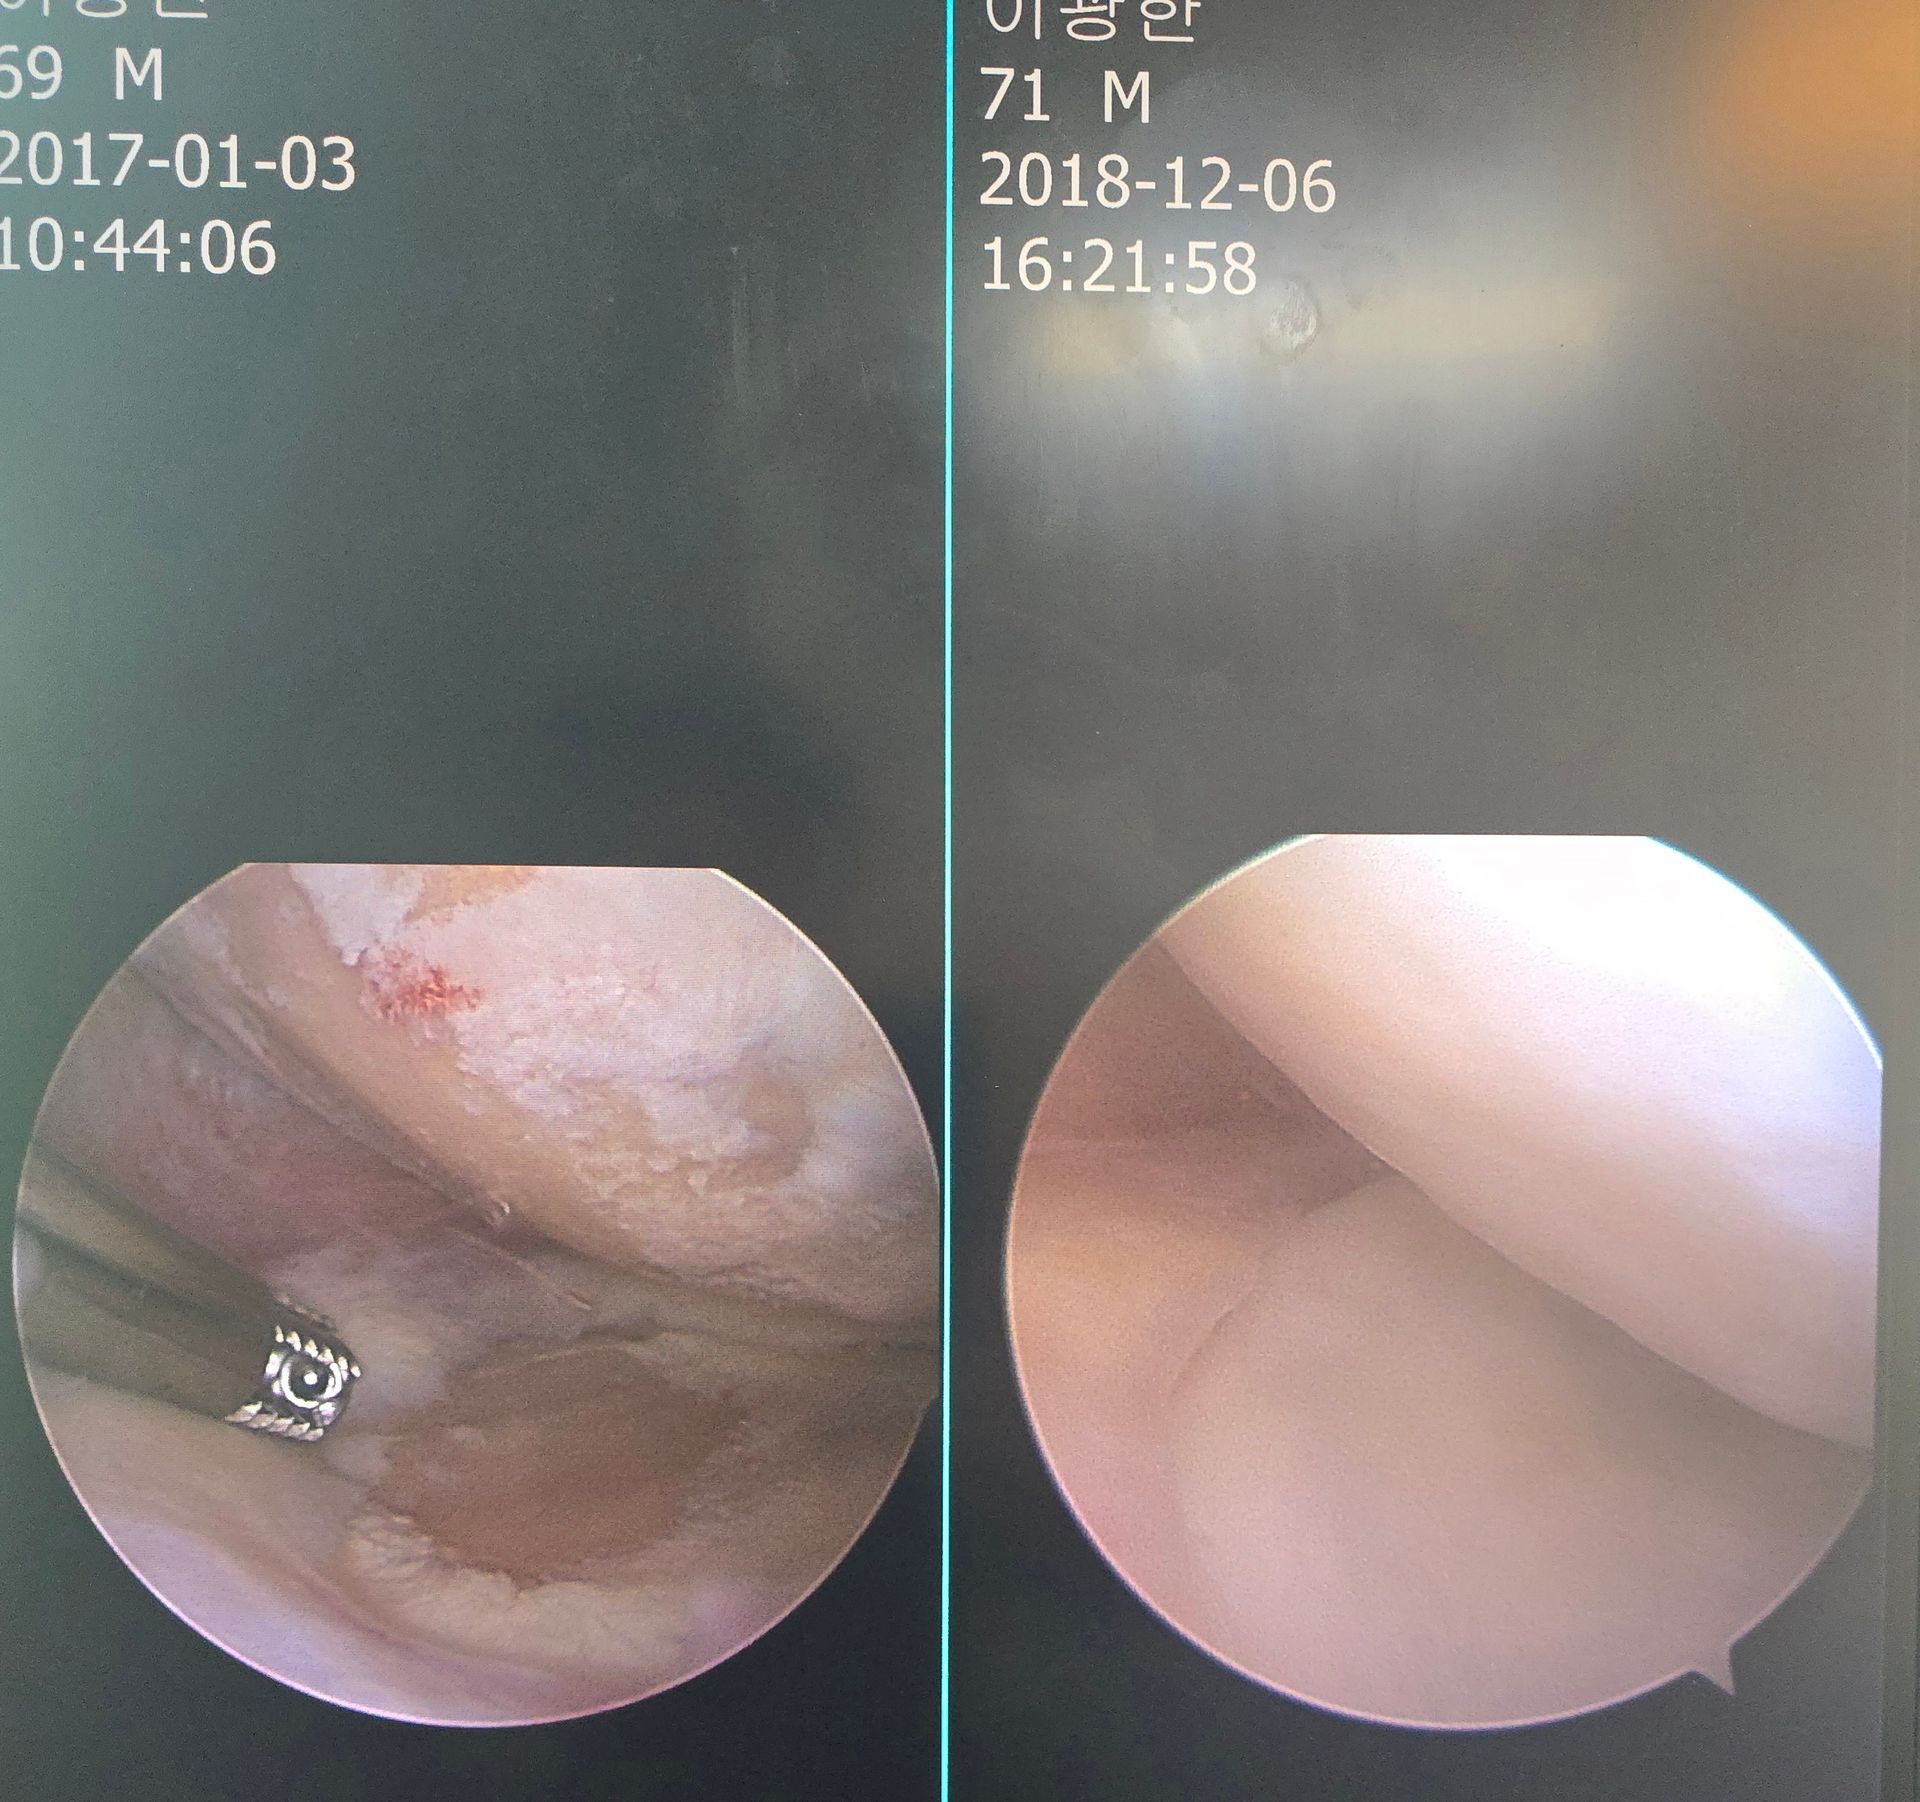

Arthroscopic Surgery

- Arthroscopic cartilage repair

- Meniscal repair

- Ligament reconstruction

- High success rates in active patients and athletes

Participants observe and engage in real-world procedures used to repair complex cartilage defects that cannot be adequately treated with conventional methods.

Emphasis is placed on restoring hyaline-like cartilage, optimizing long-term joint function, and minimizing the need for joint replacement.

CARTISTEM® Stem Cell Cartilage Restoration

- Umbilical cord blood–derived mesenchymal stem cell implantation

- Hyaline-like cartilage regeneration for knee cartilage defects